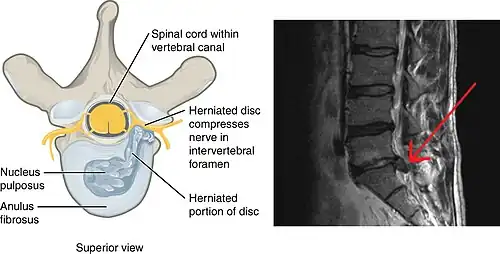

Spinal disc herniation

Spinal disc herniation pressing on one of the lumbar or sacral nerve roots is the most frequent cause of sciatica, being present in about 90% of cases.[4] This is particularly true in those under age 50.[13] Disc herniation most often occurs during heavy lifting.[14] Pain typically increases when bending forward or sitting, and reduces when lying down or walking.[13]

Intraspinal, or discogenic sciatica refers to sciatica whose pathology involves the spine. In 90% of sciatica cases, this can occur as a result of a spinal disc bulge or herniation.[14][28] Sciatica is generally caused by the compression of lumbar nerves L4 or L5 or sacral nerve S1.[29] Less commonly, sacral nerves S2 or S3 may cause sciatica.[29]

Intervertebral spinal discs consist of an outer anulus fibrosus and an inner nucleus pulposus.[14] The anulus fibrosus forms a rigid ring around the nucleus pulposus early in human development, and the gelatinous contents of the nucleus pulposus are thus contained within the disc.[14] Discs separate the spinal vertebrae, thereby increasing spinal stability and allowing nerve roots to properly exit through the spaces between the vertebrae from the spinal cord.[30] As an individual ages, the anulus fibrosus weakens and becomes less rigid, making it at greater risk for tear.[14] When there is a tear in the anulus fibrosus, the nucleus pulposus may extrude through the tear and press against spinal nerves within the spinal cord, cauda equina, or exiting nerve roots, causing inflammation, numbness, or excruciating pain.[31] Inflammation of spinal tissue can then spread to adjacent facet joints and cause facet syndrome, which is characterized by lower back pain and referred pain in the posterior thigh.[14]

Other causes of sciatica secondary to spinal nerve entrapment include the roughening, enlarging, or misalignment (spondylolisthesis) of vertebrae, or disc degeneration that reduces the diameter of the lateral foramen through which nerve roots exit the spine.[14] When sciatica is caused by compression of a dorsal nerve root, it is considered a lumbar radiculopathy or radiculitis when accompanied by an inflammatory response.[15]

Imaging modalities such as computerised tomography or magnetic resonance imaging can help with the diagnosis of lumbar disc herniation.[39] Both are equally effective at diagnosing lumbar disk herniation, but computerized tomography has a higher radiation dose.[6] Radiography is not recommended because disks cannot be visualized by X-rays.[6] The utility of MR neurography in the diagnosis of piriformis syndrome is controversial.[16]